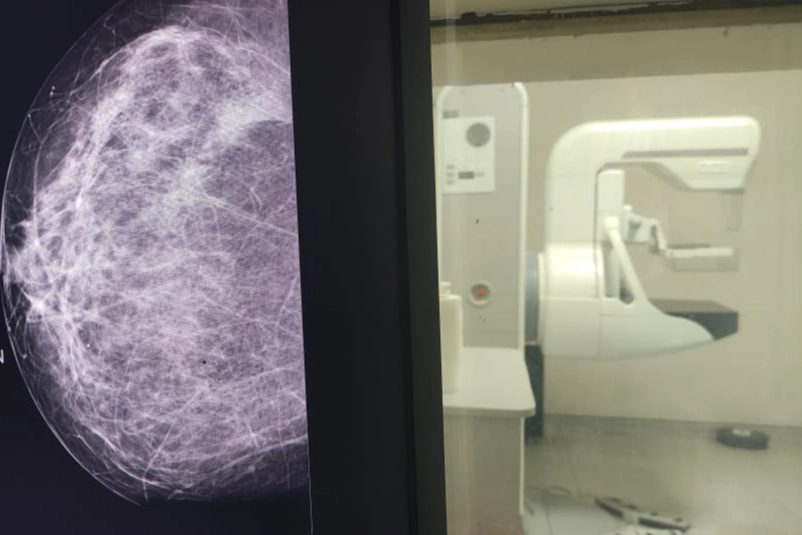

Yalnızca 5 dakika ayırıp çektirdiği mamografi sayesinde meme kanserinin erken evrede teşhis edildiğini vurgulayan Dr. Yavuz, o 5 dakikanın tüm hayatını etkileyen olumlu sonuçlara yol açtığını belirtti. Sağlıklı hayat merkezi bünyesinde meme kanserine yönelik; taramaların, elle muayenenin ve erken teşhisin önemi gibi konularda vatandaşlara yönelik eğitimler gerçekleştirdiklerini vurgulayan Dr. Yavuz, “Kendim 47 yaşındayım bu sürece kadar 2 kere mamografim olması gerekirken ben bu mamografiyi çektirmedim. Araya korkularım girdi, kaygılarım girdi, hayatımdan önemli olmayan sebepler girdi. Bir gün röntgen teknisyeni arkadaşımızın ısrarı ile kaygılarımı, korkularımı bir kenara bıraktım. 5 dakikalık sürede gittim, mamografimi çektirdim” dedi. Bu süreçte elle muayenede herhangi bir bulgu yaşamadığını dile getiren Dr. Yavuz, “Herhangi bir şikâyetim, semptomum da yoktu. Bana bir şey olmaz dedim ve ben mamografi çektirdiğimi unuttum. Ama görev yaptığım hizmet alanımda çekilen mamografi ile bana bi-rads 4c denilen meme kanseri öncesi tarama bulgusu tanısı konuldu. Ben bu tanıyla ileri tetkik ve tedavi yaptığımda meme kanseri ile karşılaştım” şeklinde konuştu. Siz de taramanızı yaptırın Çektirdiği mamografi sayesinde erken tanı aldığını ve tedavisini tamamladığının altını çizen Dr. Yavuz, “Şu anda hayatıma sağlıklı olarak devam ediyorum. İşte o beş dakika benim tüm hayatıma yön verirken, çok olumlu sonuçlara sebep oldu. Her ay yapacağınız bir elle meme muayenesi sizin hayatınızı tanımanızda, çektireceğiniz mamografi de tanınızın erken olmasına sebep olacak. Ben hekim olarak bunu yaptım. Kendi birimimde bunu başarabildim. Sizleri de her zaman KETEM birimlerinde mamografinizi çektirmeye davet ediyoruz” ifadelerini kullandı. Hızlıca tedaviye sevk edildi Dr. Mehlika Yavuz’a mamografi çektirmesi için ısrarcı olduğunu belirten Nilüfer Sağlıklı Hayat Merkezi’nde görevli Röntgen Teknisyeni Ayşen İsimbay Kızmaz ise, “İki hafta sonra çıkan sonuçta kendisinde bulgu olduğunu ve hastaneye sevki gerektiğini bildirdik. Çok şükür ileri tedavi almadan kendisi 5 dakikalık bir işlem ile hayatına dokunmuş olduk” ifadelerini kullandı.